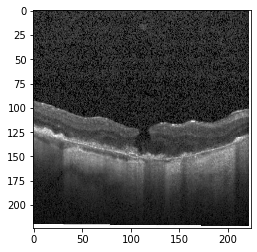

Fig 6, 7, 8 and 9 depicts the visualization of correct predictions by our proposed CNN model where fig 6 is class CNV, fig 8 is class DME, fig 7 is DRUSEN and finally, fig 9 is NORMAL. Here the first photo in every class is the original image. The LIME map of our suggested model’s prediction is shown in image B whereas in image C the positive region is highlighted in specific sections on the original image. For Image D we have increased the number of features from 5 to 10 thus more regions have been predicted as the positive region which is highlighted in green. After increasing the features from 5 to 10, some of the regions are predicted wrongly. The red regions represent the output of incorrect prediction. The following image represents the Grad-CAM heatmap highlighting the regions with our model’s prediction.